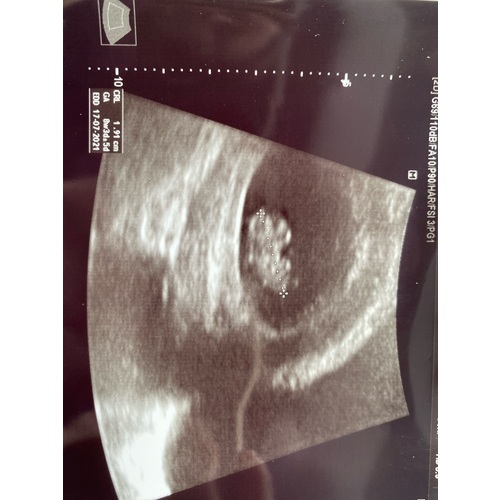

Ik dacht 8 weken te zijn bij de echo ze hadden me alleen iets terug gezet naar 7+4. Nu alweer een goede termijn echo gehad en vandaag alweer 11+4.

Helaas moeilijk tezien gisteren echo gehad ban 8+5 maar mijn baarmoeder ligt nog wat verder naar achter dus niet zn hele helderen echo maar hartje klopt en alles was goed 😍😍